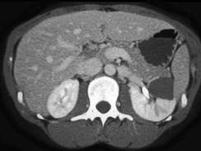

问题 女,35岁,请根据所示图像,选择最可能诊断 ( )

选项 A、左侧肾盂旁囊肿 B、左侧囊性肾癌 C、左侧高密度肾囊肿 D、左侧肾积水 E、左侧单纯性肾囊肿

答案 C